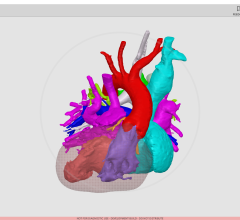

A key component of this transformation is a new super-computing technology called CT-fractional flow reserve (FFR), which may offer a noninvasive alternative to catheter-based FFR, the current gold standard for determining if a stent is required for a particular lesion. Experts at SCCT said this, combined with CT myocardial perfusion imaging, will be more accurate and help eliminate the need for nuclear perfusion imaging.